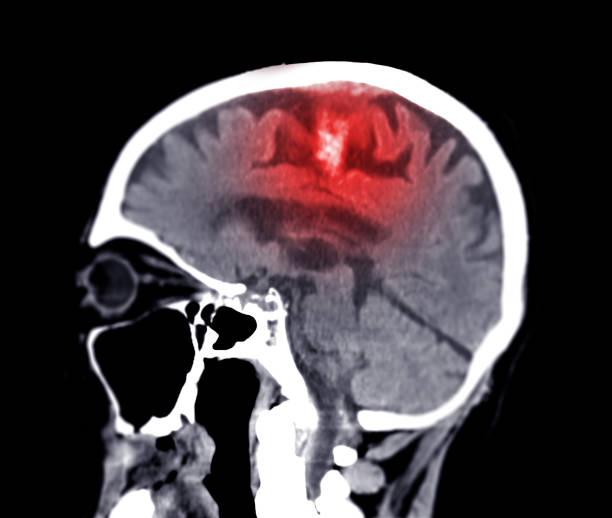

The ketogenic diet is highly effective as a cure for epilepsy, and works to reduce or eliminate seizures even in situations where anticonvulsant pharmaceuticals don’t work. The vast majority of people who follow this diet consistently for at least 3-6 months – especially children – either become completely seizure-free or have a significant reduction in seizures. Noteworthy clinical improvements are often observable within just days of starting the ketogenic diet, though positive changes in hypsarrhythmia – chaotic, disorganized electrical activity in the brain of epileptic patients – may take a few months to improve. Thus, it’s key to be patient and consistent, and to be aware of other seizure management tools during the adjustment period with the ketogenic diet.